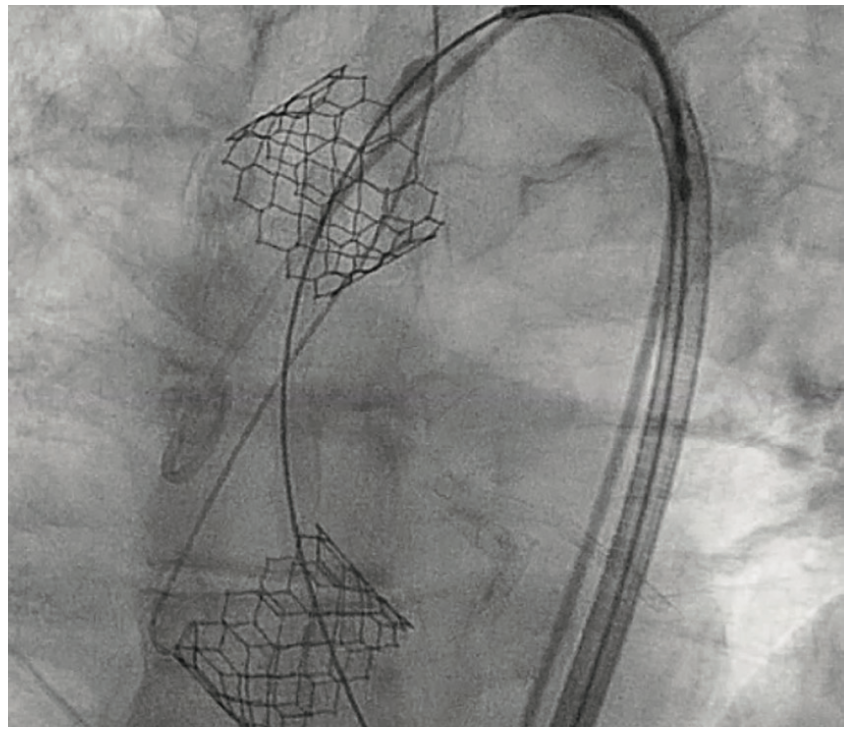

During the TAVR procedure, a Sapien 3 26 mm valve was loaded over a Safari wire (Boston Scientific) and advanced into the aortic annulus under fluoroscopy, with good planar angle positioning confirmed using contrast injection. After valve placement, rapid ventricular pacing was performed and the valve was deployed. However, immediately following deployment, the valve embolized into the ascending aorta. The valve was carefully pulled distally and secured just proximal to the origin of the right brachiocephalic artery. It was dilated with an extra 4 mL volume with two inflations performed. To confirm the patency of the right subclavian artery and the right brachiocephalic artery, access was subsequently obtained in the right radial artery, and no difference in the arterial pressure was noted as the catheter was advanced from the right radial artery into the aortic root. A second Sapien 3 26 mm valve was then loaded over the Safari wire and was similarly advanced into the aortic annulus under fluoroscopy, with good coplanar angle positioning confirmation via contrast injection. After rapid ventricular pacing, the second valve was deployed without issue. A post procedure aortogram confirmed good valve positioning, the absence of significant paravalvular leak, and patency of the left coronary artery. A limited echocardiogram also confirmed good valve positioning, the absence of paravalvular leak, and the absence of pericardial effusion. The patient tolerated the procedure well and left the cardiac catheterization laboratory in a stable condition. After chest x-ray confirmed stable positioning of the embolized valve in the ascending aorta, the patient was discharged on postoperative day one with a scheduled follow-up visit in three weeks.